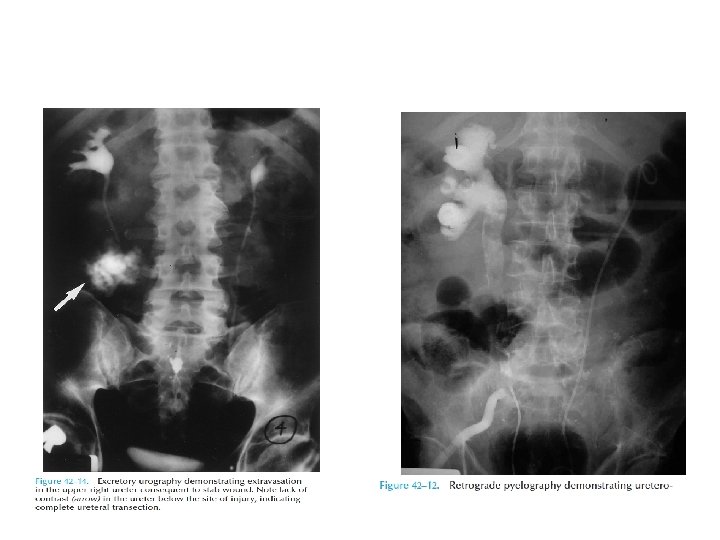

Diagnosis • Presense of hematuria(non specific) • Imaging – IVU – CT urogram – RGP – Antegrade ureterography • Intraoperative recognisation

Hematuria and ureteral injury • Nonspecific indicator • 25 – 45% patients donot demonstrate even microscopic hematuria. • Being suspicious for it is the only way you will catch it.